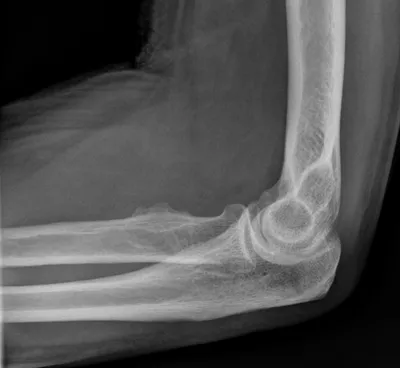

Synovial Osteochondromatosis of Elbow

Elbow

4/10/2026